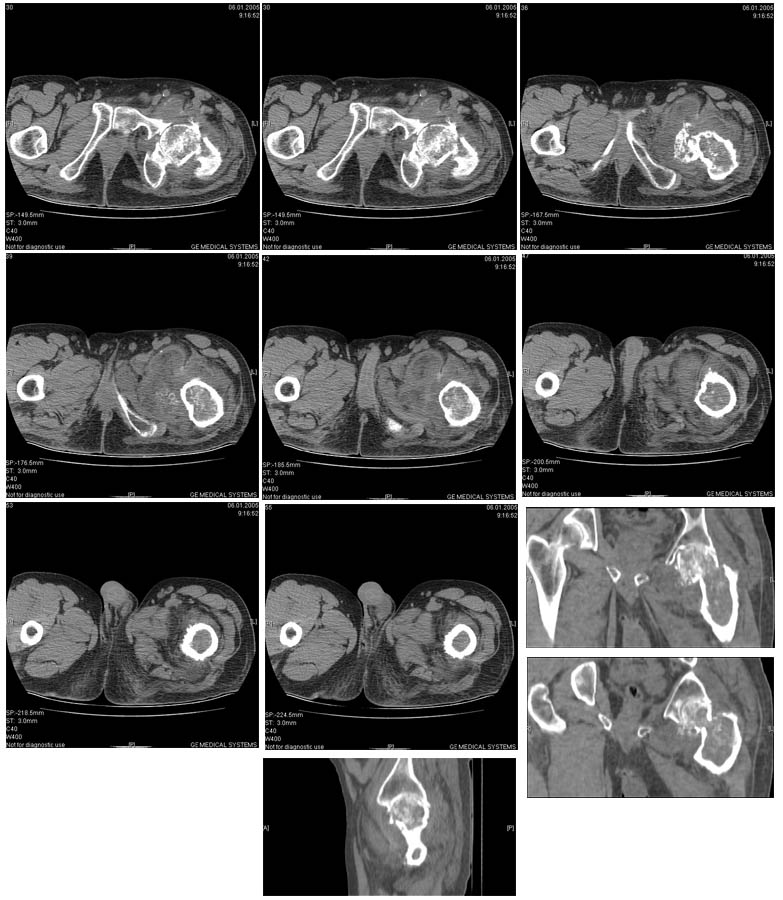

И снова вопрос по эндопротезированию: Пациенту 51 год. Болен с 2000 г, когда отметил умеренные, нараостающие боли в в/3 левого бедра, прогрессирующую контрактуру лев Т/Б сустава.

05.12.04 после падения на бедро боли резко усилились, нога стала неопорной. На рентгенограмме обнаружен патологический перелом шейки бедренной кости. Обследован в отделении костной онкологии. Результат биопсии: асептический некроз проксимального отдела бедренной кости. Вопрос: выбор технологии эндопротезирования - цементная или бесцементная версия. Заранее благодарю! С уважением,А.В.Владзимирский

Проксимальный отдел бедра не виден достаточно на представленных рентгенограммах; но то, что видно, как раз наводит на мысли о цементной фиксации - цилиндрический канал, измененный calcar, кистозные изменения в области большого вертела и т.д.

Как то очень подозрительно выглядит проксимальный отдел бедра для такого очень простого гистологического заключения. Вы уверены, что гистология настолько благополучна и в каком варианте она выполнялась: пункционная или открытая с забором костного блока? Не уверен на все сто , но область проксимального отдела бедра - одно из излюбленных мест для гигантоклеточной опухоли, которая зачастую озлакочествляется (имел два подобных наблюдения). Из своей практики могу сказать, что, к сожалению, информативность пункционной биопсии не сравнима с открытой техникой. Поэтому прежде чем решать цементный или бесцементный протез использовать, я бы повторил биопсию в сочетании со сканированием скелета, сывороточная щелочная фосфатаза, кальций, фосфор сыворотки, СОЭ, С- реактивный белок,

Вполне вероятно, что разговор может пойти об опухолевом протезе или Вагнере...

Soglasen s Евгений И Чекашкин, proximal Femur does not look right. Sarcoma? Pagets, Osteomyelitis?. Technicality of the implantaion will be dependent upon underlying pathology, and the surgeon's level of comfort.

Ацетабулум как-то странно выглядит, с дыркой.

Действительно, проксимальный отдел бедра выглядит подозрительно. По-моему напоминает болезнь Педжета. Кстати, гистологическое заключение в таком случае часто звучит как "хроническое воспаление", "асептический некроз с элементами лейкоцитарной инфильтрации" и т.п. Далеко не все патоморфологи имеют достаточный опыт для дифференцировки костной патологии.

Однако, вне зависимости от диагноза, проблема "с цементом или без" остается. Онко-эндопротезы (так же как и ревизионные) тоже могут быть бесцементной фиксации. И в нешей клинике есть положительный опыт их применения. Поразительно, насколько полярными могут быть мнения в этом вопросе, причем аргументация ссылками на литературу практически лишена смысла - достаточно много статей с равной степенью уверенности пропогандирующих и то и другое. Ссылки на собственный опыт тоже имеются разные. Лично я больше склоняюсь к бесцементной технике. Однако советую запастись и цементными компонентами и окончательно решить, что применять во время операции.